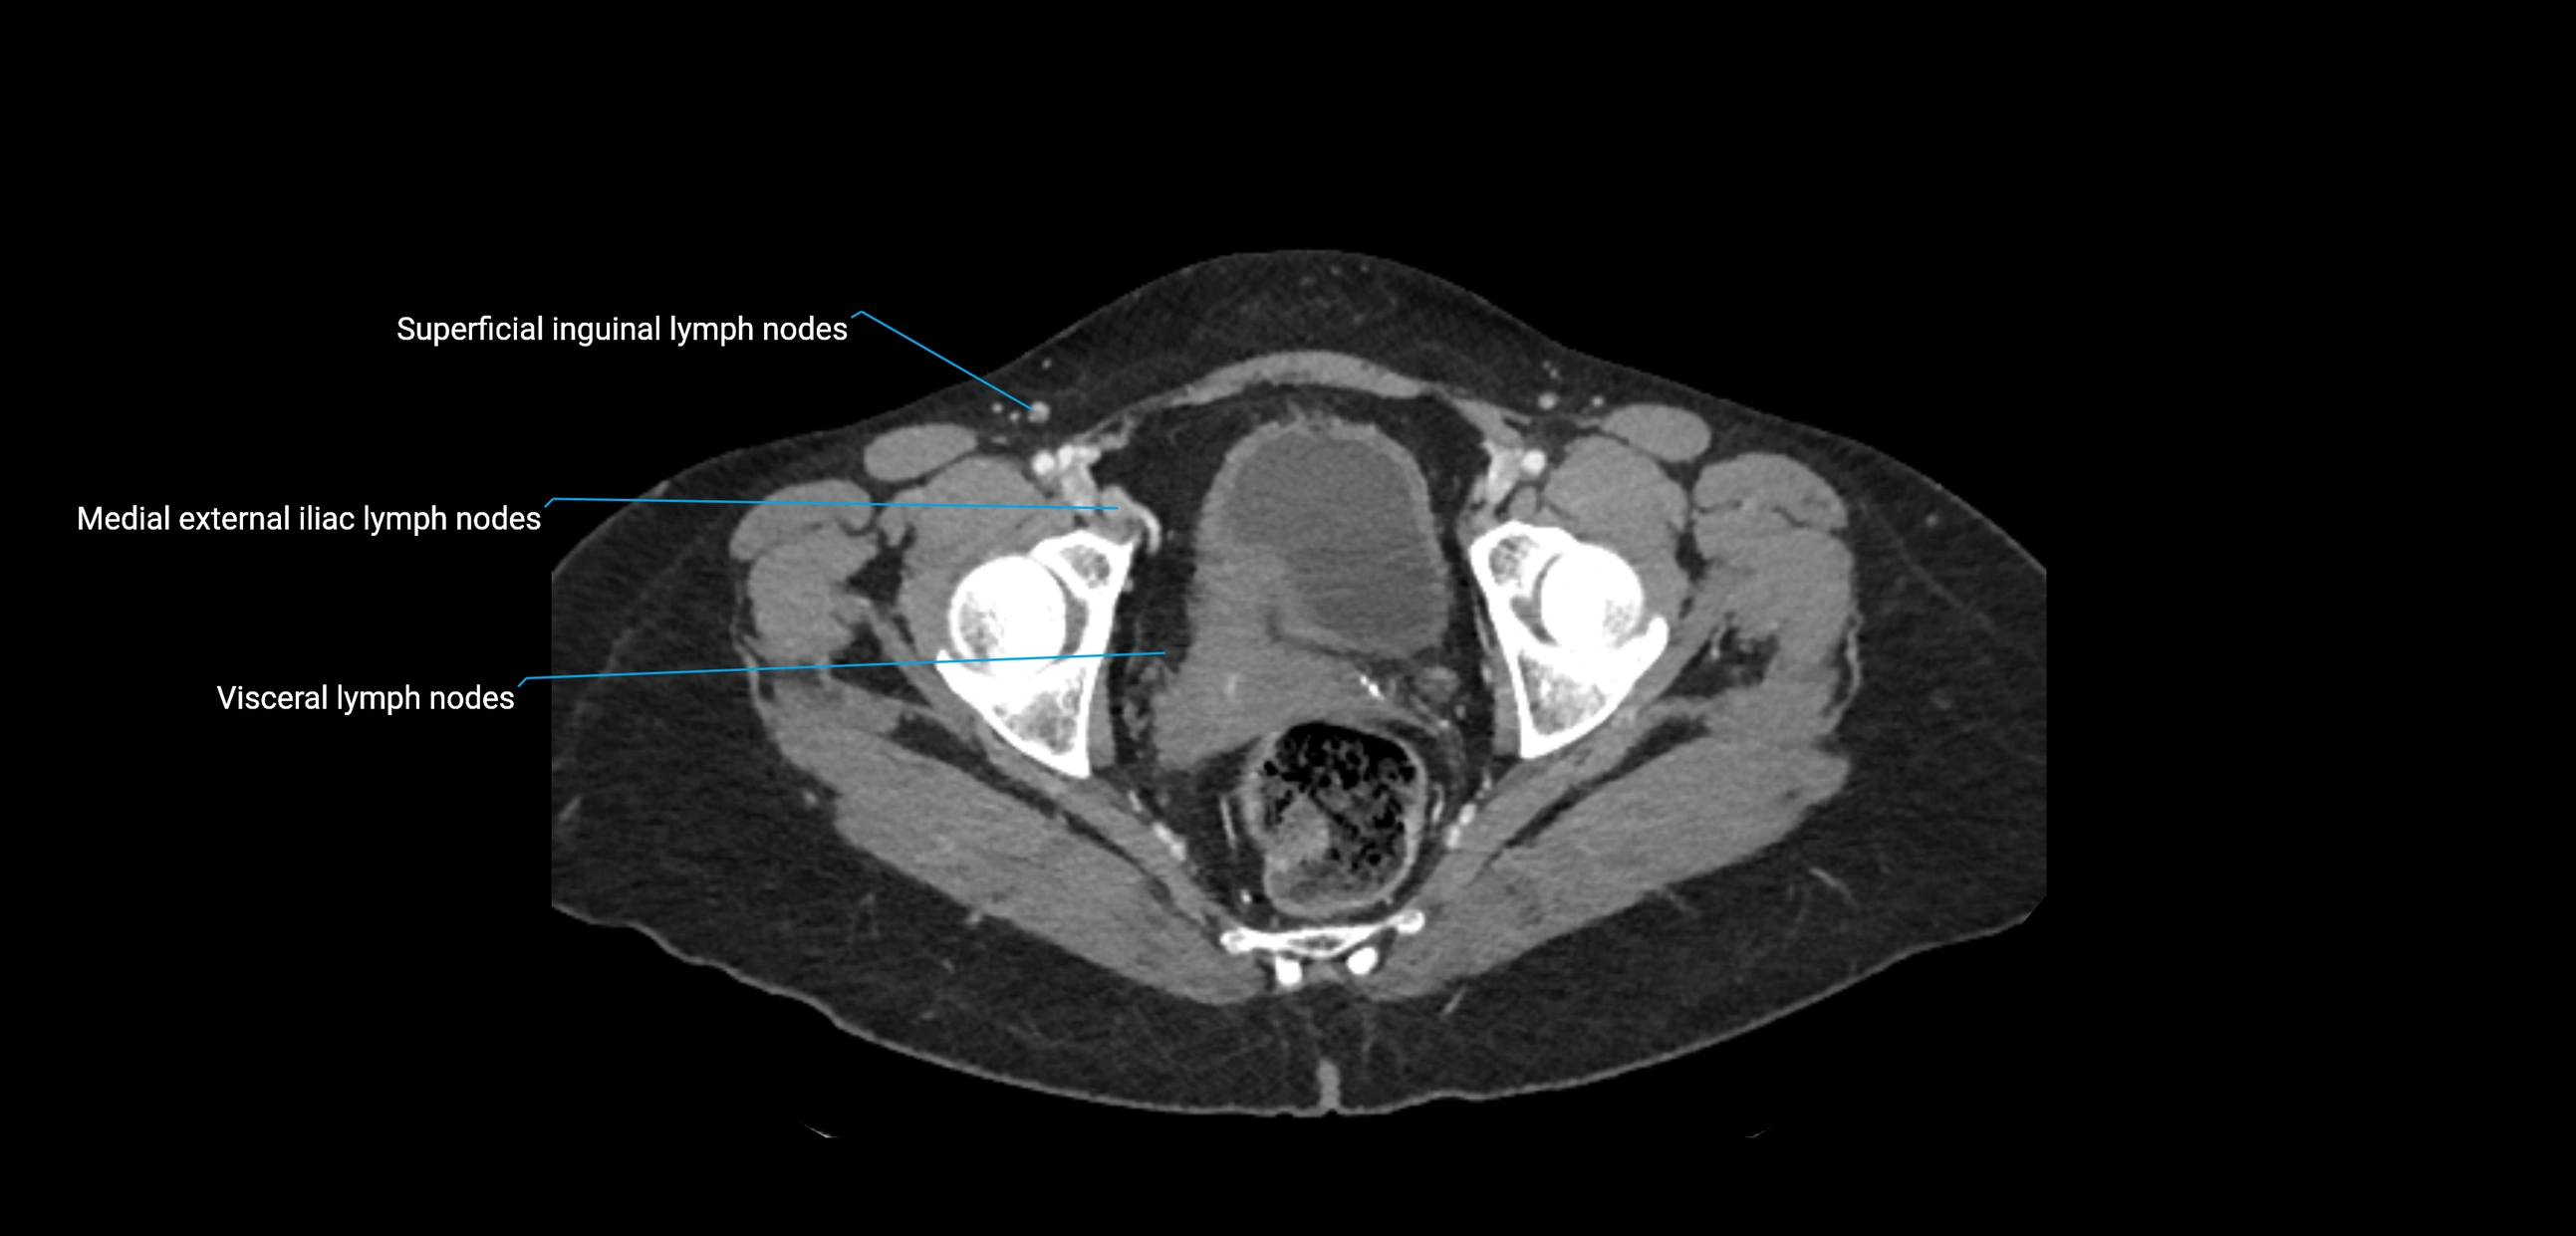

CT Appearance

CT Pre-Contrast:

• Nodes appear as soft-tissue density nodules adjacent to the aorta and IVC

• Calcification may be seen in chronic infections (e.g., tuberculosis)

CT Post-Contrast:

• Normal nodes enhance homogeneously

• Malignant nodes may show heterogeneous enhancement, central necrosis, or conglomerate formation

• Size >1 cm short axis is suspicious, though morphology and distribution are equally important